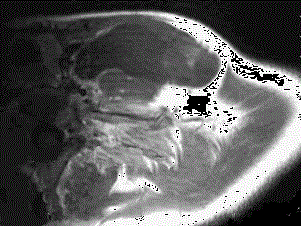

问题 37岁女性,左侧颈部肿块渐进性增大,无压痛,局部皮温不高,CT、MRI扫描如图所示,请选择正确的描述或诊断 ( )

选项 A、MRI的TWI呈高信号,其内可见分隔 B、考虑为淋巴管囊肿 C、增强扫描未见强化 D、MRI的TWI呈低信号 E、CT发现左侧颈后三角区可见低密度肿块影

答案 ABCDE